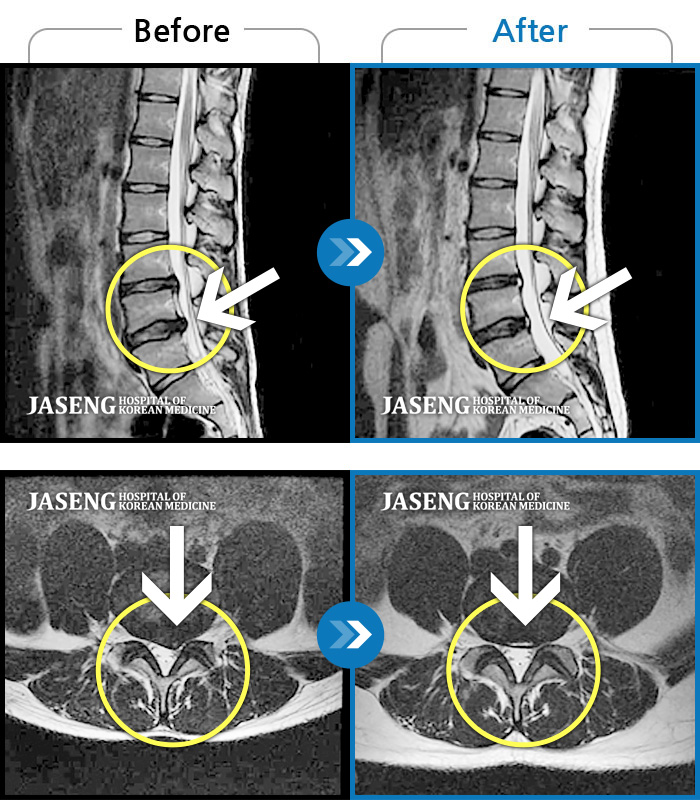

허리디스크

안산 · 김민수 원장

왼쪽 허리에서 다리로 내려가는 심한 통증으로 서 있거나 오래 걷지 못하였습니다.

촬영시기

2022.02.12 ~ 2023.02.17

2023.02.24